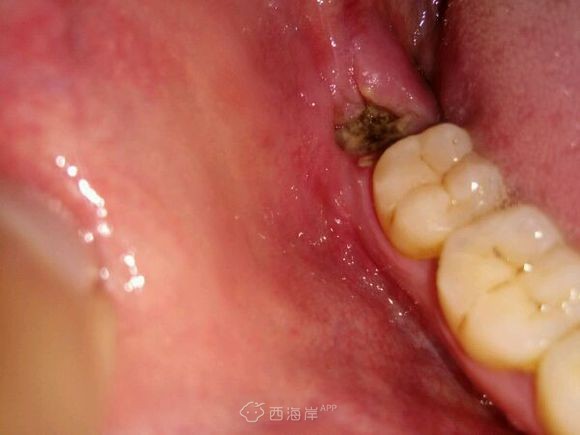

拔牙第三天,希望快点好

这样就能早点忘记让人恐惧的那一天